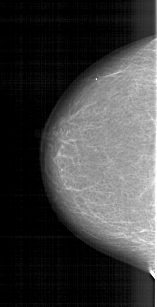

A_1422_1.LEFT_CC

LEFT_CC LINES 5206 PIXELS_PER_LINE 2656 BITS_PER_PIXEL 12 RESOLUTION 43.5 NON_OVERLAY